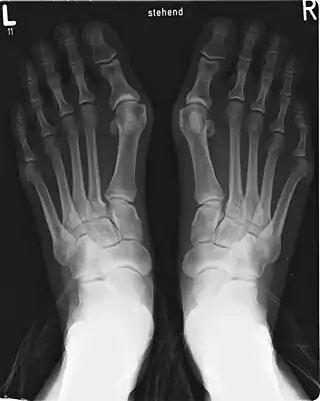

- Hallux valgus, o juanetes: Desviación del primer dedo del pie fuera de la línea media, acompañado además de una protuberancia (exostosis) en la articulación metatarsofalángica, constituyendo la patología más frecuente de la articulación, con una prevalencia del 28,4 % de la población general.[100][101] Existirían dos formas de hallux valgus, uno congénito, de aparición en la infancia y con una prevalencia similar entre sexos, y otra principalmente adquirida, que en su gran mayoría afecta al pie egipcio, con mayor prevalencia en mujeres, y cuyas causas sería el calzado inadecuado o brotes reumáticos (artritis reumatoide).[89] También se señala como causa traumatismos, pie plano, trastornos neuromusculares, trastornos de tejido blando o inestabilidad de la articulación metatarsofalángica.[102]